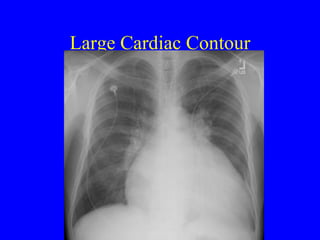

Large Cardiac Contour

Large cardiac contour AP portable magnifies Lordotic film magnif Kyphotic film minim Rotation changes Pericardial effusion looks like cardiomegaly